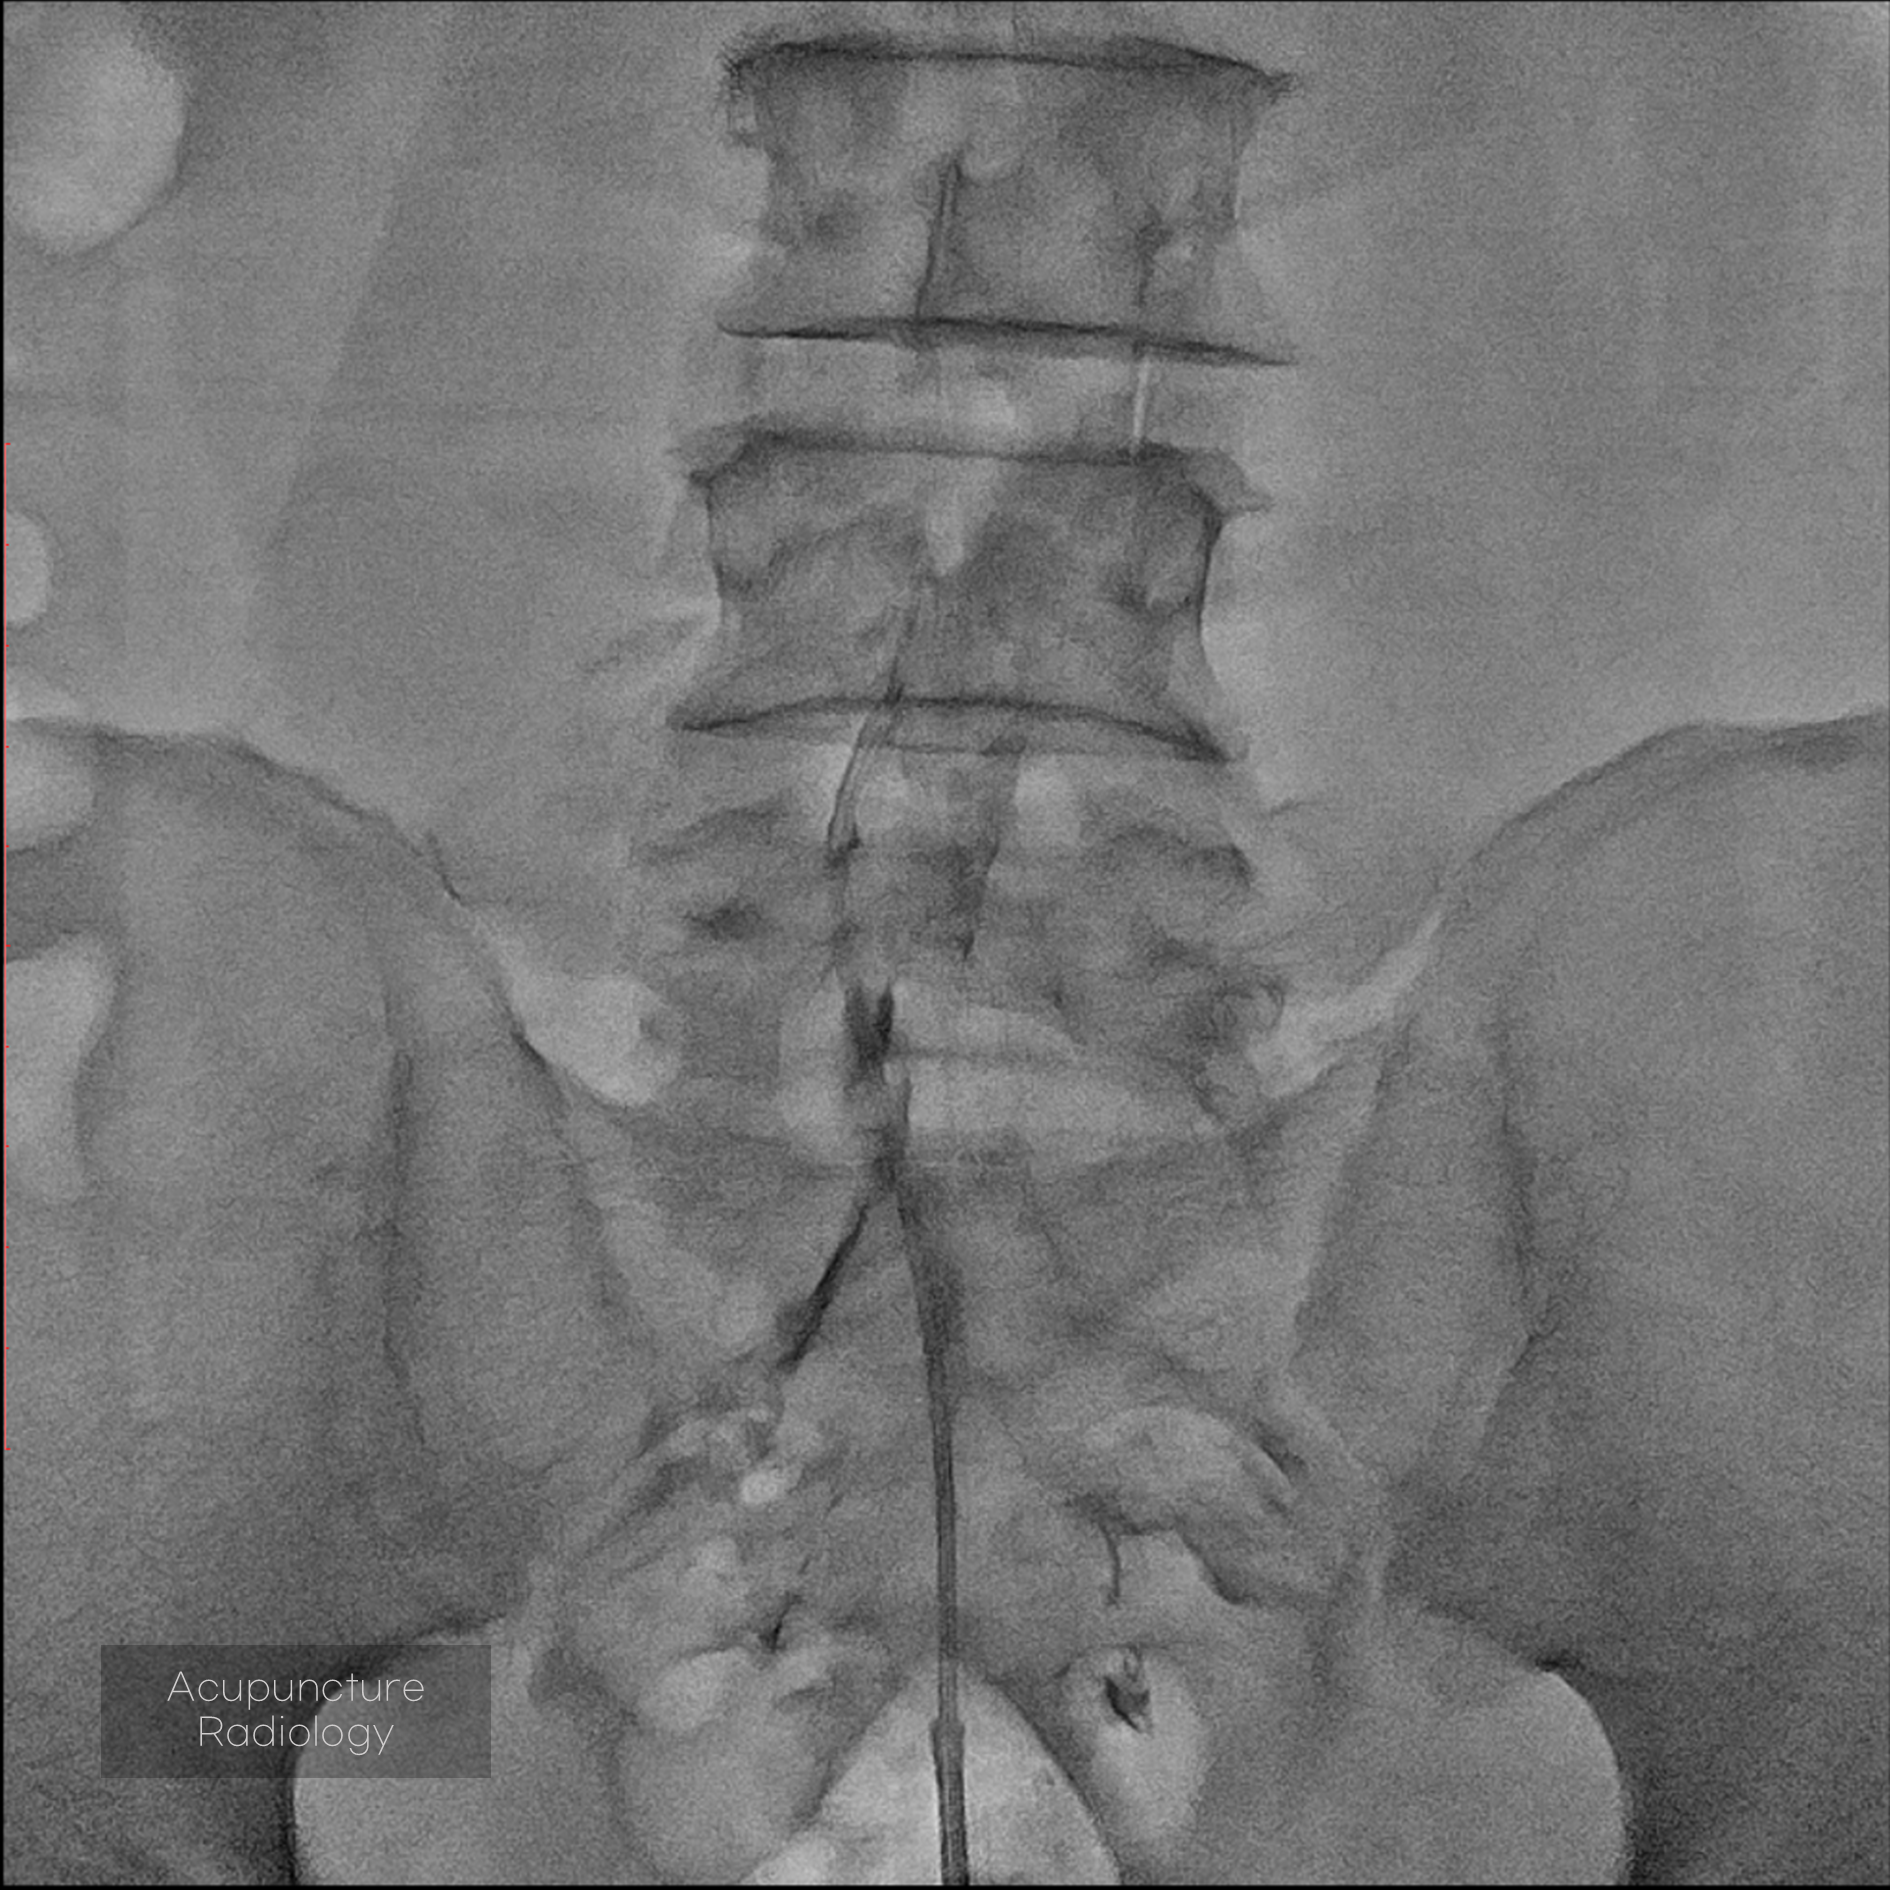

경막외 유착박리술, Epidural Neuroplasty